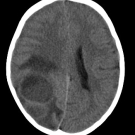

A 14-year-old girl presented with an ongoing problem with dental crowding in the area of the upper central incisors; a previous CT scan of the head had identified a cyst emanating from the area of the...

12/27/2020